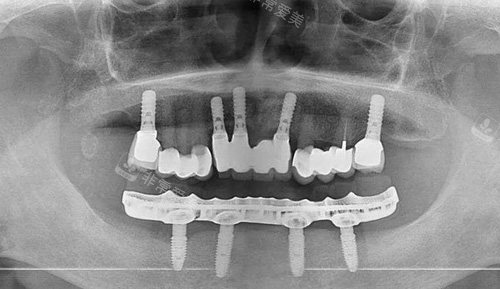

其次,从结果和舒适度来看,种牙可能会稍微好一些。种牙是通过植入人工牙根的方式来固定假牙,与自然牙更为接近,具有更好的咀嚼功能和稳定性。相比之下,镶牙需要磨削周围的健康牙齿,可能会对健康牙齿造成一定程度的损害。

此外,就费用而言,种牙相对于镶牙可能稍微昂贵一些。种牙手术需要较高的技术水平和设备,因此费用相对较高。而镶牙则是通过制作义齿并固定在牙齿上的方式,相对来说费用可能更为实惠。

综上所述,种牙在结果和舒适度上可能更胜一筹,但费用相对较高;而镶牙则相对便宜一些,适用范围更广,但可能对周围牙齿造成一定的损害。因此,具体选择种牙还是镶牙,应该根据个人的口腔情况、经济能力和需求来进行综合考虑和选择。如果您有牙齿缺失问题,建议询问牙医,根据个人情况选择适合的修复方式,恢复口腔健康和美观。